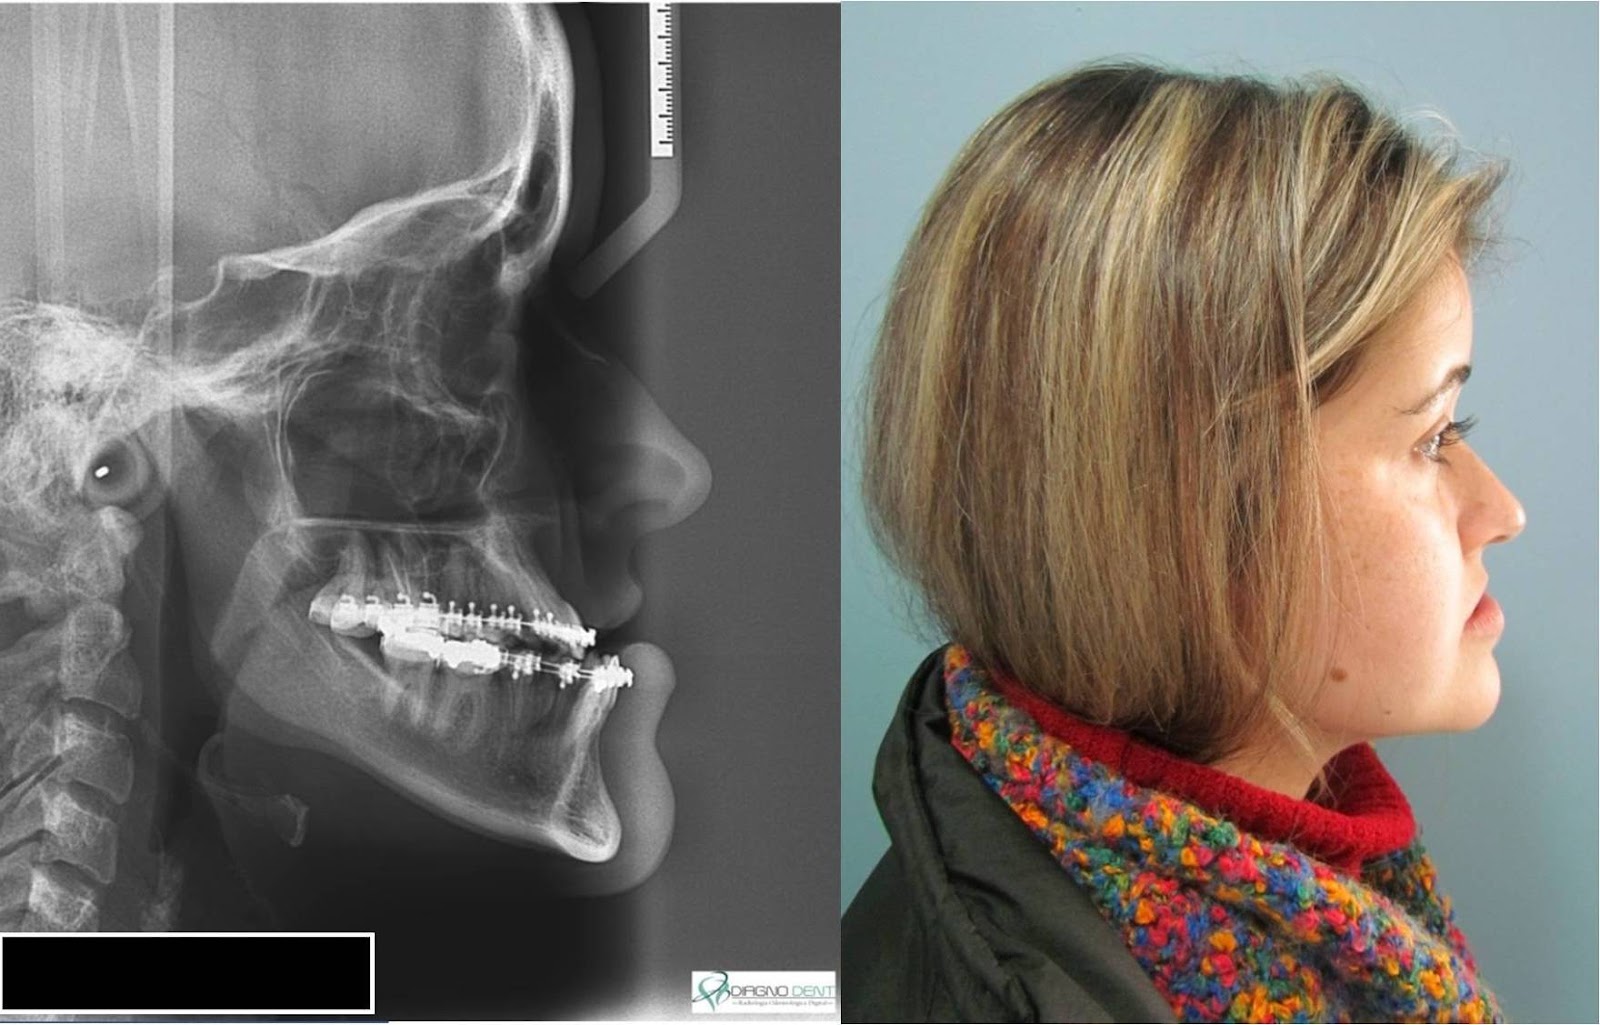

| Teleradiografia de perfil e perfil de face pós-operatórios |